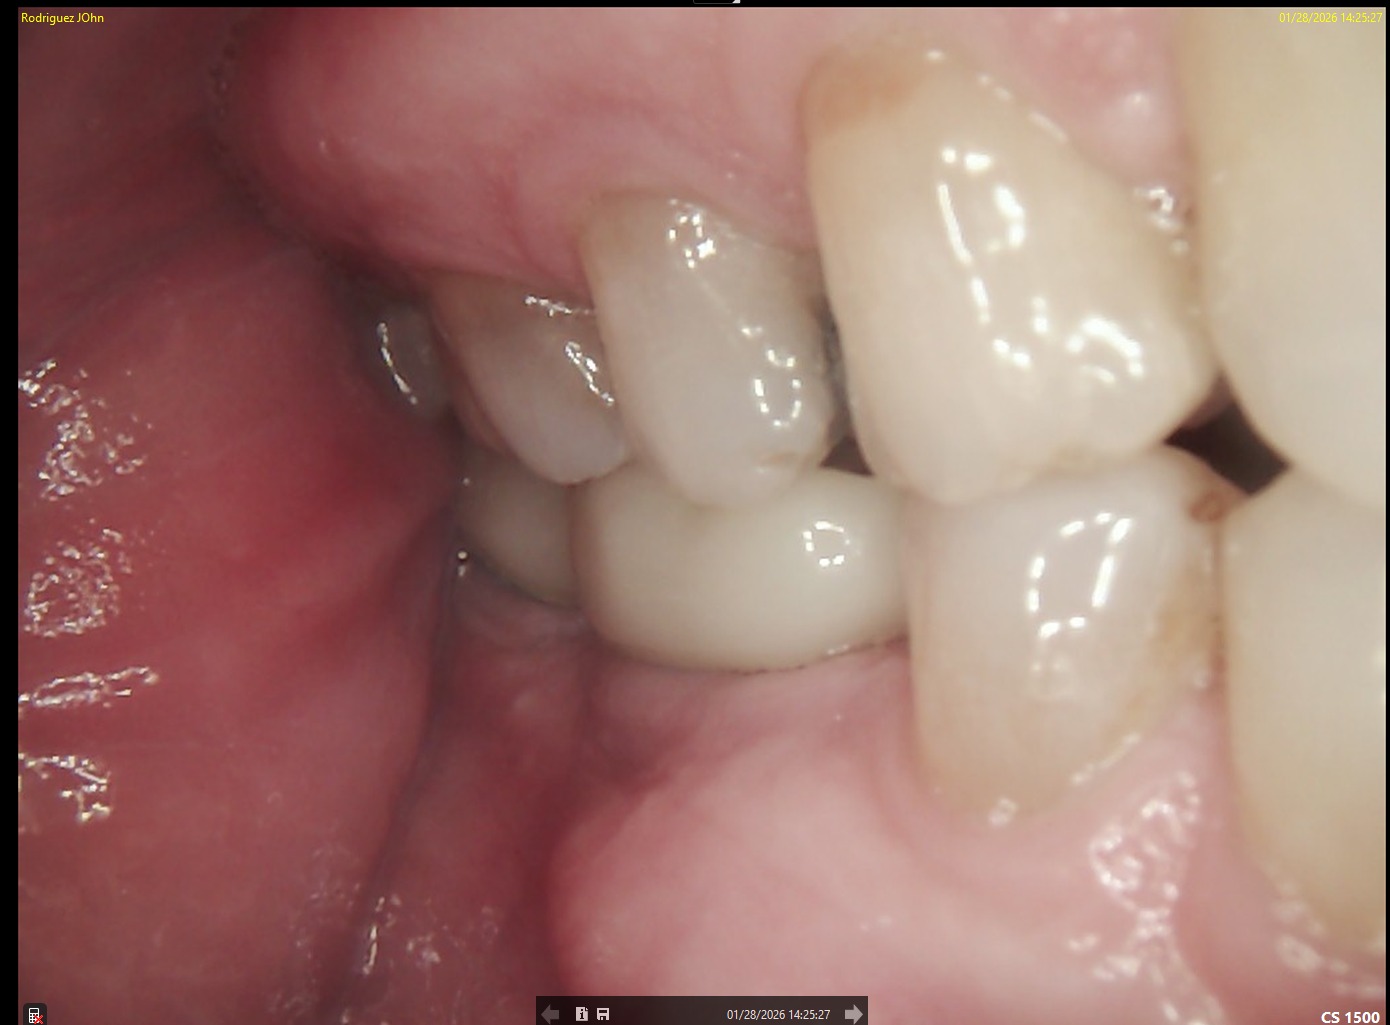

FOLLOW-UP - 2026

At the three-year follow-up:

• Peri-implant bone levels remained stable

• Soft tissues demonstrated healthy morphology and color

• The restorations maintained functional integrity under occlusal load

Both clinical and radiographic evaluations confirmed long-term hard and soft tissue stability, validating the treatment protocol and implant system used.